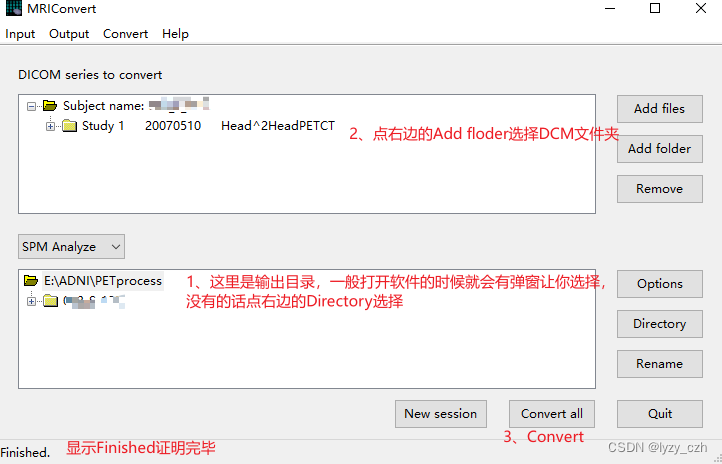

1、使用MRIConvert处理DCM

打开程序选择输出输入目录并且选择SPM Analyze如下图所示